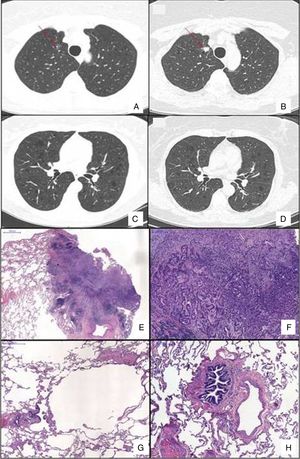

Chest HRCT scans showing diffuse cystic lung disease and a solitary pulmonary nodule (red arrow) in the beginning of follow-up (A and C) and five years later (B and D). (A) Regular and thin-walled pulmonary cysts and a 10mm pure ground-glass nodule in the right upper lobe. (B) CT image at the same level as Fig. 1A after five years of follow-up showing a significant increase in the size of the nodule (13mm) and change in its composition (a solid nodule). (C) Random and multiple thin-walled cysts. (D) Stability of diffuse pulmonary cysts five years later. (E) A low-power view of the tumor with a dense area of scarring. (F) Invasion area with desmoplastic tissue, irregular glands and micropapillae. (G) Constricted airway and peribronchiolar alveolar overdistension. (H) Bronchiole with submucosal fibrosis and focal inflammatory cell infilltrate. (H&E stains, original magnification (A) ×10, (B) ×50, (C) ×40 and (D) ×100).

After 5 years of follow-up, PFTs were stable and there was an increase in the nodule size (13mm), with a solid composition (Fig. 1). There was a mild increase of glycolytic metabolism (SUV 2.6) on the combined positron emission tomography/CT. There was no evidence of lymph node enlargement or extrapulmonary disease. A right upper lobectomy with lymphadenectomy was performed after an adenocarcinoma has been confirmed in the intraoperative frozen section. Histopathological analysis revealed a predominantly acinar invasive adenocarcinoma, with lepidic and micropapillary components, which was classified as Stage IA (T1aN0M0). The lung parenchyma around the tumor revealed a heterogeneous small airway disease characterized by variable narrowing of the small airways, abnormal bronchioles with subepithelial fibrosis and scattered chronic inflammatory cells, associated with peribronchiolar alveolar overdistension, which was consistent with constrictive bronchiolitis (Fig. 1).

A 59-year-old asymptomatic woman was referred to our outpatient clinic to investigate a diffuse cystic lung disease (DCLD) incidentally found on abdominal computed tomography (CT). Her past medical history revealed obstructive sleep apnea and Paget disease, for which she used zoledronic acid. She denied smoking and had no relevant exposure. Physical examination was normal and her peripheral oxygen saturation was 98% on room air. Chest high-resolution CT (HRCT) revealed multiple thin-walled pulmonary cysts diffusely distributed in both lungs and a 10mm ground-glass nodule in the right upper lobe (Fig. 1). Pulmonary function tests (PFTs) showed normal spirometry, air trapping (RV, 166% of predicted; RV/TLC ratio, 0.51) and a mild reduction in DLCO (60% of predicted). Serum markers of inflammatory activity, protein electrophoresis, alpha 1 antitrypsin serum dosage were normal, and antinuclear antibodies, rheumatoid factor, anti-Ro/SSA and anti-La/SSB were negative. The serum level of vascular endothelial growth factor-D was 407pg/mL and abdominal ultrasound and scintigraphy of salivary glands were normal. She refused to undergo a surgical lung biopsy for diagnostic elucidation. The nodule remained stable during the follow-up.